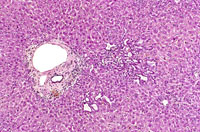

Two local aggregates of proliferating bile ducts within the hepatic lobule.